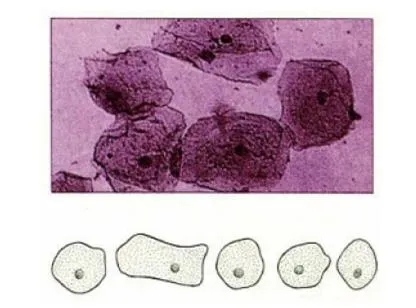

[요약] 혈액 중 혈구의 염색에 사용되는 염색약으로, 핵의 염색이 뚜렷한 시약이다.

혈액 중 혈구의 염색에 사용되는 염색약으로, 핵의 염색이 뚜렷한 시약이다. 반응했을 때, 붉은 색을 띠는 에오신과 대표적으로 푸른색을 띠는 시약인 메틸린 블루가 있기 때문에 뚜렷한 색을 관찰할 수 있는 시약이다. 핵은 뚜렷하게 염색시키지만 세포질은 잘 염색시키지 못하며, 약한 산성의 환경에서 가장 높은 활성을 나타내기 때문에 호중구와 호염기 형태의 과립 백혈구는 염색이 어렵다. 붉은 색을 띠는 부분이 백혈구의 세포질이고, 보라색을 띠는 부분이 백혈구가 된다.